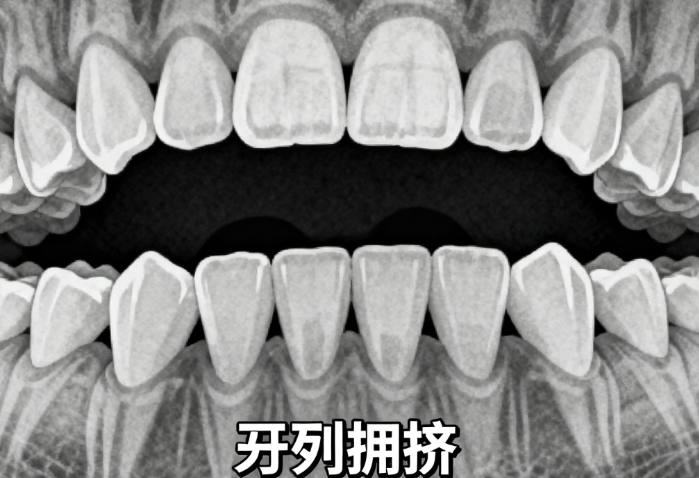

4. 廣州穗華口腔(天河院區(qū)):

連鎖品牌,正畸科是重點(diǎn)科室,80%醫(yī)生擁有本科及以上學(xué)歷;醫(yī)生擅長(zhǎng)自鎖托槽矯正,針對(duì)牙列擁擠實(shí)例采用“輕力矯正”,患者反饋“療程比預(yù)期縮短1 - 2個(gè)月”的占比約70%。